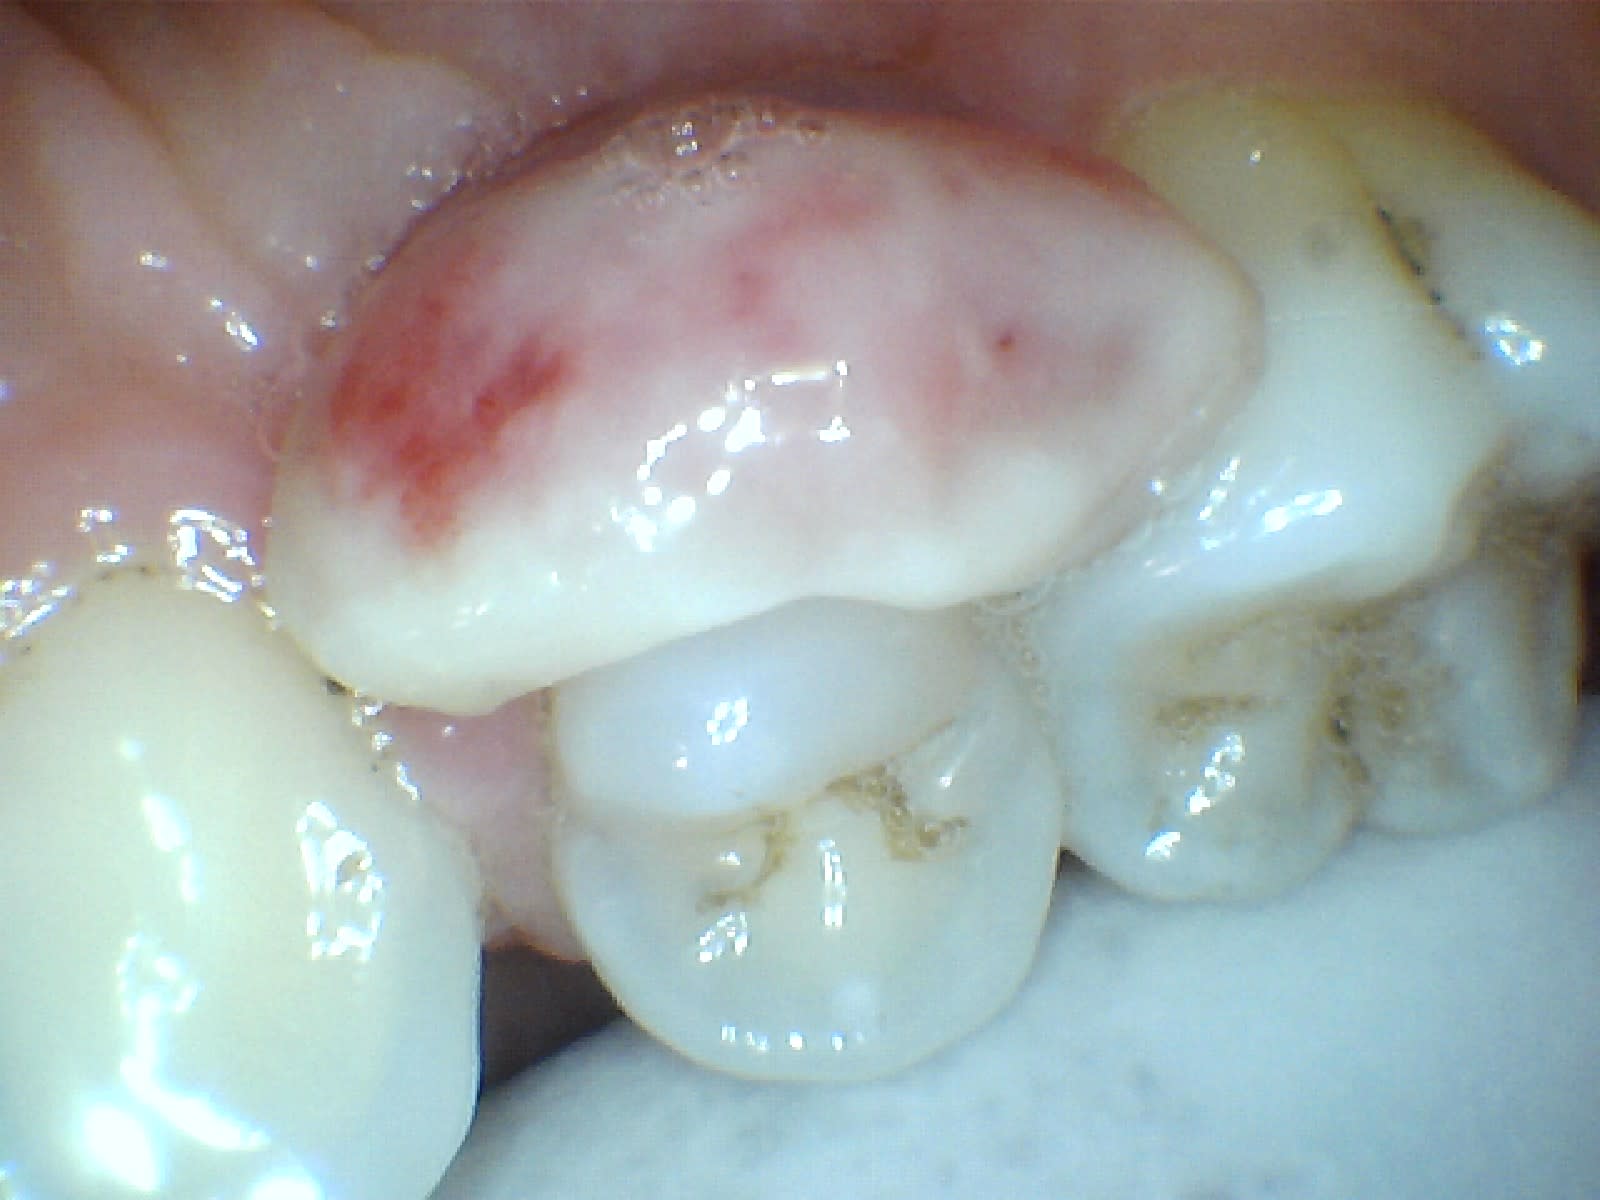

au niveau de la resolution ca donne ca. C'est clair que c'est pas parfait mais je pense qu'on voit ce qu'on veut montrer